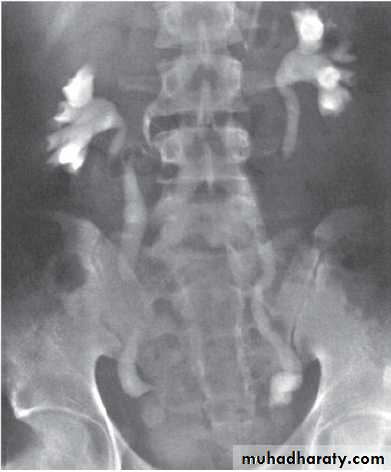

Grading of VUR

The degree of reflux is graded I–V.

Grading is based on the appearance of contrast agent in the collecting system during voiding cystourethrography (VCUG(.

The VCUG:

the definitive examination

to diagnose and grade reflux and establish reversible causes

must include a voiding phase:

in some cases, reflux may be seen only during the elevated intravesical pressures associated with micturition.

in visualizing the urethra, may allow the diagnosis of outflow obstruction to be made (e.g., posterior urethral valves).

MCUG